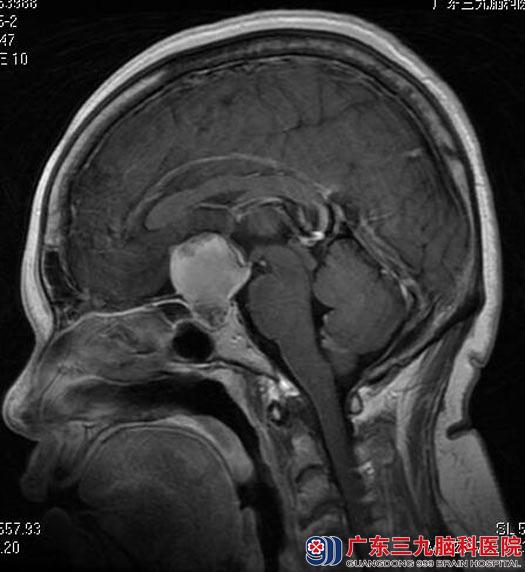

住院在广东三九脑科医院综合神经外科。头颅MR检查结果:鞍内及鞍上示一不规则异常信号影,范围约为2.4cm×2.7cm×3.1cm,考虑颅咽管瘤可能;头颅CTA检查显示:鞍区(鞍上为主)占位性病变,前交通动脉偏左侧囊状突起影,考虑动脉瘤(小型);内分泌检查报告:垂体前叶功能低下。予左甲状腺素口服治疗,两周后患者甲功基本正常。

▲术前MR